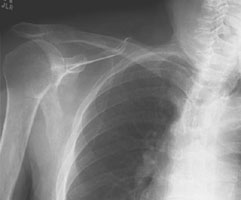

- Click on the image for a larger versionBAxillary radiograph of the shoulder. This view demonstrates the anterior dislocation of the humeral head (towards the coracoid).